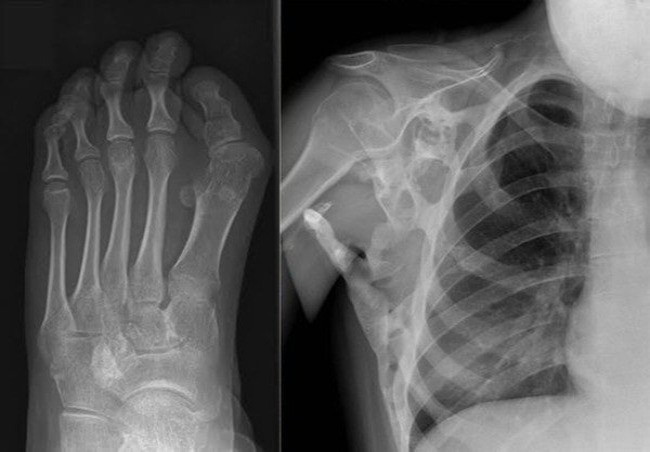

- Chụp X-quang xương: Đây là cách tối ưu nhất để xác định được số lượng các xương tổn thương, sự xâm lấn phần mềm.